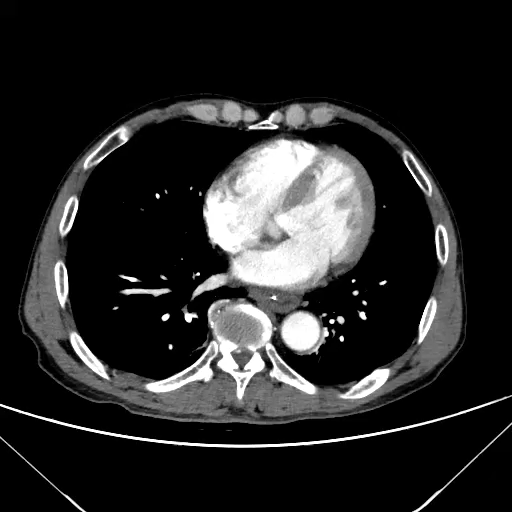

辅助检查:CT平扫及增强检查

相隔两小时后行CT增强

动脉期

静脉期

延迟期